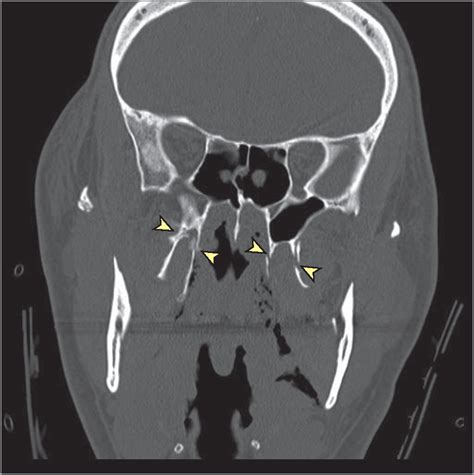

Before we even think about ICD-10 codes, let’s get a solid grasp on what we’re even talking about. The pterygoid plates, guys, are essentially two thin, wing-like bony projections that extend downwards from the sphenoid bone, which is located at the base of your skull. Think of them as a crucial part of the posterior and lateral walls of the nasal cavity and the infratemporal fossa. They’re pretty deep in there, which means fractures to this area aren’t exactly common sniffles; they usually result from significant trauma. The pterygoid plates have several important functions. They serve as attachment points for muscles crucial for chewing (the pterygoid muscles, surprise surprise!) and also play a role in the movement of the soft palate. Because of their location, injuries to the pterygoid plates can be associated with a range of other facial and cranial injuries, making diagnosis and coding a bit more complex. It’s not just about the plate itself; it’s about understanding the surrounding structures and potential associated trauma. This area is also rich in blood vessels and nerves, so any fracture here needs careful evaluation by medical professionals to rule out more serious complications. Understanding the anatomy is key to appreciating the significance of a fracture here and why precise coding is so vital. It’s like knowing the foundation of a building before you start fixing the walls!

Now for the nitty-gritty: finding the actual fracture of pterygoid plate ICD 10 codes. The ICD-10-CM (International Classification of Diseases, Tenth Revision, Clinical Modification) system is designed to be incredibly detailed, which is great for specificity but can sometimes feel like navigating a maze. When it comes to fractures of the pterygoid plate, these aren’t typically listed as a standalone, distinct diagnosis code. Instead, they usually fall under broader categories related to skull and facial bone fractures. This is where clinical documentation becomes super important, guys. The physician’s notes need to be specific enough to guide the coder to the most appropriate code. Generally, you’ll be looking at codes within the S02.- series , which covers fractures of the skull and face. Specifically, codes related to other facial bone fractures might be relevant. For instance, S02.8 covers ‘Other fractures of facial bones’. This code might be used if the pterygoid plate fracture is documented but doesn’t fit neatly into more specific facial bone fracture codes. However, the key is to look for further specificity if available. Sometimes, a pterygoid plate fracture might be documented alongside other injuries, and the coder needs to determine if a more specific code for, say, a temporal bone fracture (which can involve the pterygoid structures) or a fracture of the base of the skull applies. It’s crucial to always refer to the official ICD-10-CM coding guidelines and the most up-to-date code set , as these can be updated annually. Coders often use coding software and lookup tools, but understanding the underlying anatomical structures and the potential codes is paramount. Remember, the goal is to find the code that most accurately reflects the physician’s diagnosis based on the documentation. If the documentation clearly states ‘fracture of the pterygoid plate,’ and there isn’t a more specific code that encompasses this, then a code like S02.8 might be the closest fit, possibly with additional codes to describe associated conditions or complications. Always code to the highest level of specificity documented by the provider . This might involve looking at subcategories within S02.8 if they offer more detail related to the location or type of fracture. Don’t forget to consider external causes of injury codes (V, W, X, Y codes) and status codes (Z codes) as well, as these provide a complete picture of the patient’s encounter. For fracture of pterygoid plate ICD 10 , thorough documentation is your best friend!